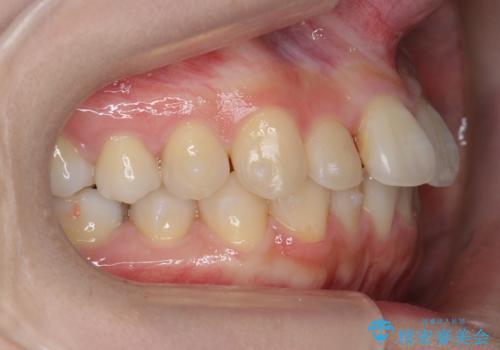

軽度の前歯のがたつき 下の前歯が生まれつき少ない

- 前歯のがたつきを主訴に来院。

下の前歯が生まれつき3本でした。

そのため、上の前歯が少し余るような形で出っ歯になっていたため、スペースを作って引っ込めています。

下を3本でそのまま並べてあるため、上下の正中は合いません。

合わせようとすると抜歯か、下の隙間を無理やり開けてブリッジとなりますが、そこまでするメリットがないため、下はそのままの歯の数を生かしています。